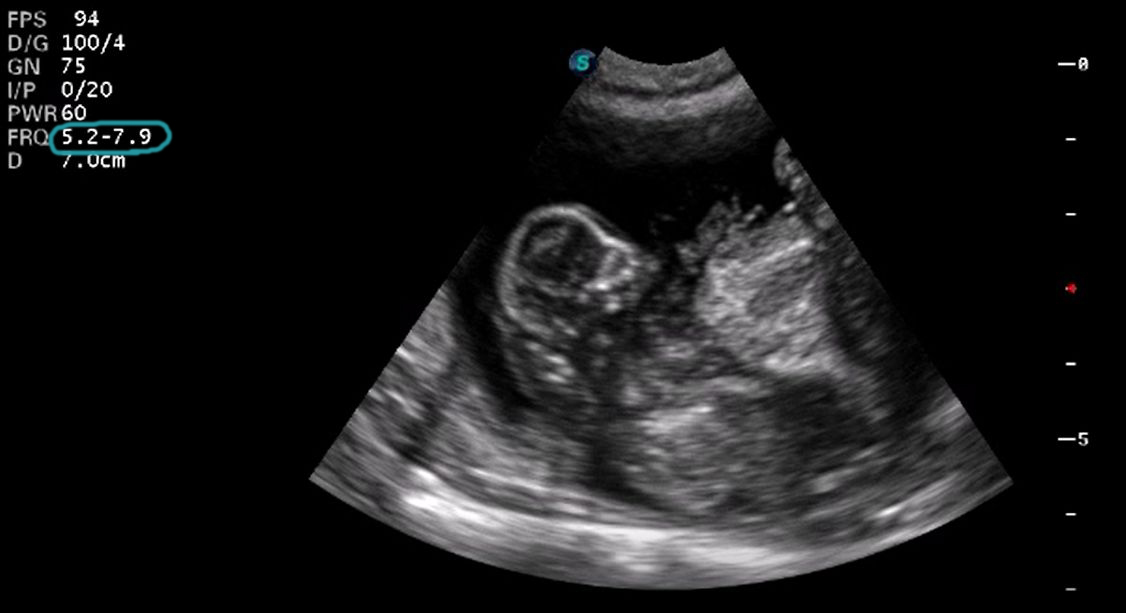

Below are some examples of scan images taken at higher frequencies. The scanning frequency has been circled in blue. The below images are captured at high resolution.

High frequency scan image